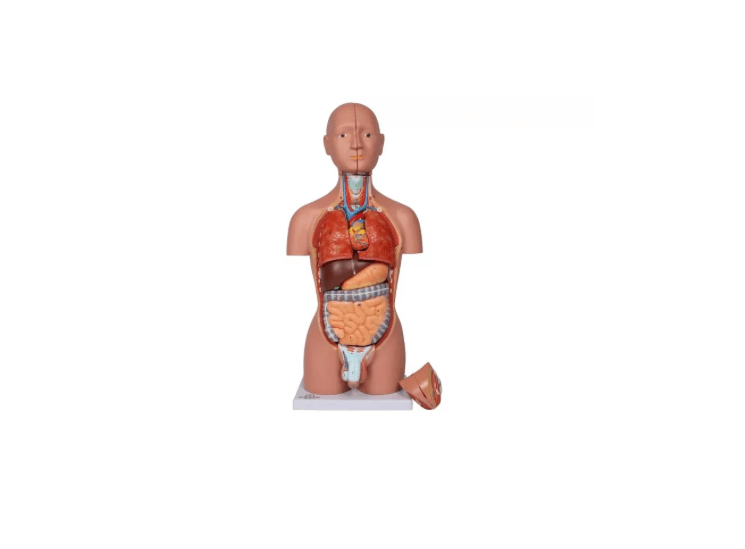

Dieses Torso-Modell in ca. ½ Lebensgröße bietet eine kompakte und dennoch äußerst detailreiche Darstellung der menschlichen Anatomie. Ideal geeignet als Schreibtischmodell, für den Anatomieunterricht oder zur Patientenaufklärung, vermittelt es anschaulich die Lage und den Aufbau innerer Organe – inklusive männlicher und weiblicher Geschlechtsorgane. Die verschiedenen Komponenten lassen sich entnehmen und untersuchen, was das Modell besonders nützlich für den Einstieg in die menschliche Anatomie macht. Lieferung erfolgt auf stabiler Grundplatte inklusive beschrifteter Anleitung.

Modellteile im Überblick:

Grundkörper mit zwei Kopfhälften

Eine Kopfhälfte mit herausnehmbarem Gehirn

Zwei Lungenhälften

Herz (zweiteilig zerlegbar)

Magen

Leber

Darmpaket mit abnehmbarem Blinddarmdeckel

Weibliche Geschlechtsorgane (zweiteilig)

Männliche Geschlechtsorgane (zweiteilig)